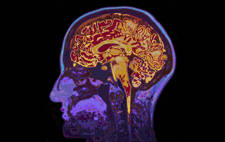

Al usar tecnología moderna como el TAC de o la resonancia magnética nuclear, los científicos han desarrollado una comprensión más profunda de lo que está ocurriendo en nuestros cerebros cuando meditamos, de forma similar a cómo los científicos han analizado la creatividad en nuestros cerebros .

Dichas investigaciones han demostrado que la meditación puede tener efectos positivos tanto fisiológicos como psicológicos. Algunos de los efectos fisiológicos positivos incluyen un menor estado de excitación física, menor frecuencia respiratoria, menor frecuencia cardíaca, cambios en los patrones de ondas cerebrales y menor estrés.

La meditación no solo hace maravillas para el dolor de lumbago persistente, la ciencia también afirma que la meditación ayuda a controlar el dolor mental y emocional. Sentarse en silencio y observar tus propios pensamientos durante unos pocos minutos durante el día puede, literalmente, cambiar la forma en que funciona tu cerebro, así como la forma en que responde a las situaciones de dolor físico, como los dolores de lumbago crónico.

Diversas investigaciones han demostrado claramente que las técnicas de meditación pueden tener una serie de efectos positivos en la salud general y el bienestar psicológico. Múltiples exploraciones cerebrales de estudios concretos, revelaron que los participantes pudieron aumentar significativamente su capacidad para lidiar con situaciones mentalmente incómodas y estresantes de maneras saludables, utilizando la meditación diaria para el control de dichas situaciones.